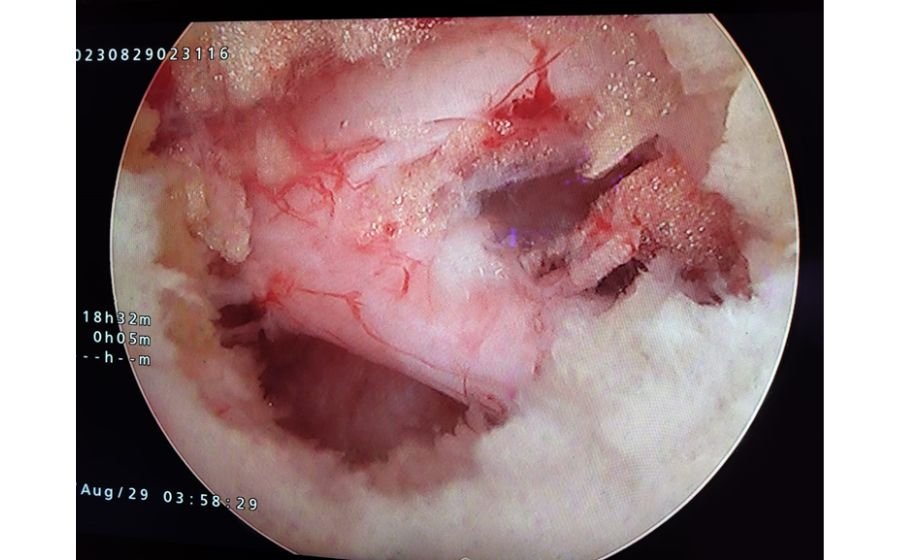

Minimally Invasive Spine Surgery (MISS) (Key Hole Surgery)

Minimally invasive spine surgery uses small incisions (small scar) and specialized instruments to treat spinal problems with far less disruption to muscles and surrounding tissues. These techniques help relieve nerve compression, stabilize the spine, or remove damaged discs while reducing blood loss and postoperative pain. MISS allows faster recovery, shorter hospital stay, and a quicker return to normal activities compared to traditional surgery. It is commonly used for disc herniation, stenosis, instability, and certain fusion procedures.